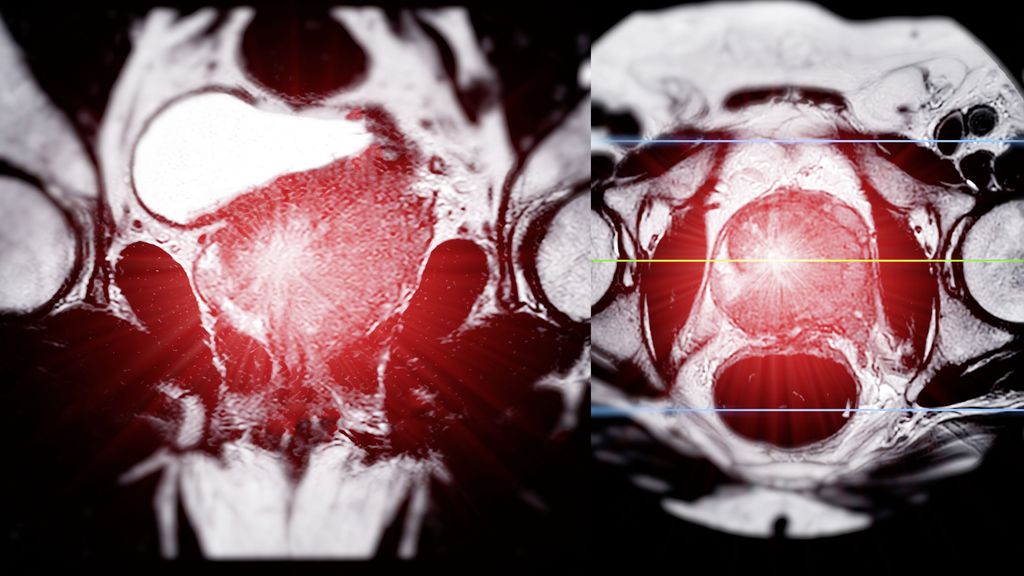

Für die Auswahl der Systemtherapie wird die PSMA-PET-Bildgebung zunehmend wichtig (PSMAddition-Studie) und molekulare Marker (HRR-Alterationen, PTEN-Verlust) können Subgruppen von Personen identifizieren, die von einer zielgerichteten Strategie profitieren können.